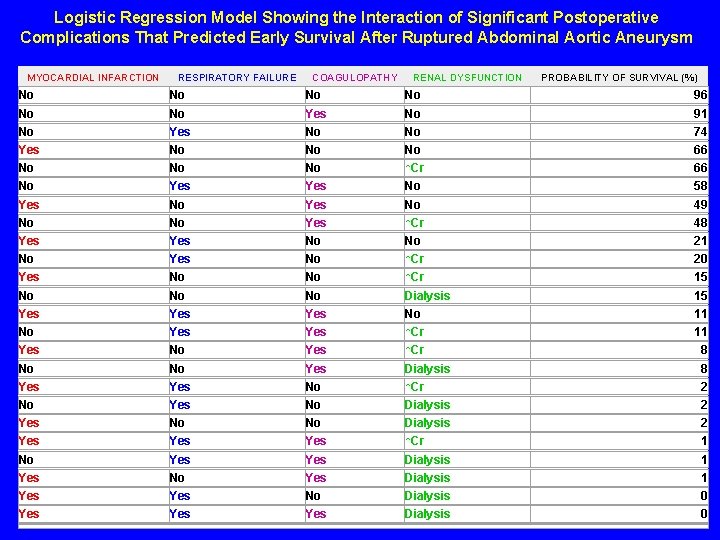

Logistic Regression Model Showing the Interaction of Significant Postoperative Complications That Predicted Early Survival After Ruptured Abdominal Aortic Aneurysm MYOCARDIAL INFARCTION RESPIRATORY FAILURE COAGULOPATHY RENAL DYSFUNCTION PROBABILITY OF SURVIVAL (%) No No 96 No No Yes No 91 No Yes No No 74 Yes No No No 66 No No No ↑Cr 66 No Yes No 58 Yes No 49 No No Yes ↑Cr 48 Yes No No 21 No Yes No ↑Cr 20 Yes No No ↑Cr 15 No No No Dialysis 15 Yes Yes No 11 No Yes ↑Cr 11 Yes No Yes ↑Cr 8 No No Yes Dialysis 8 Yes No ↑Cr 2 No Yes No Dialysis 2 Yes No No Dialysis 2 Yes Yes ↑Cr 1 No Yes Dialysis 1 Yes No Dialysis 0 Yes Yes Dialysis 0